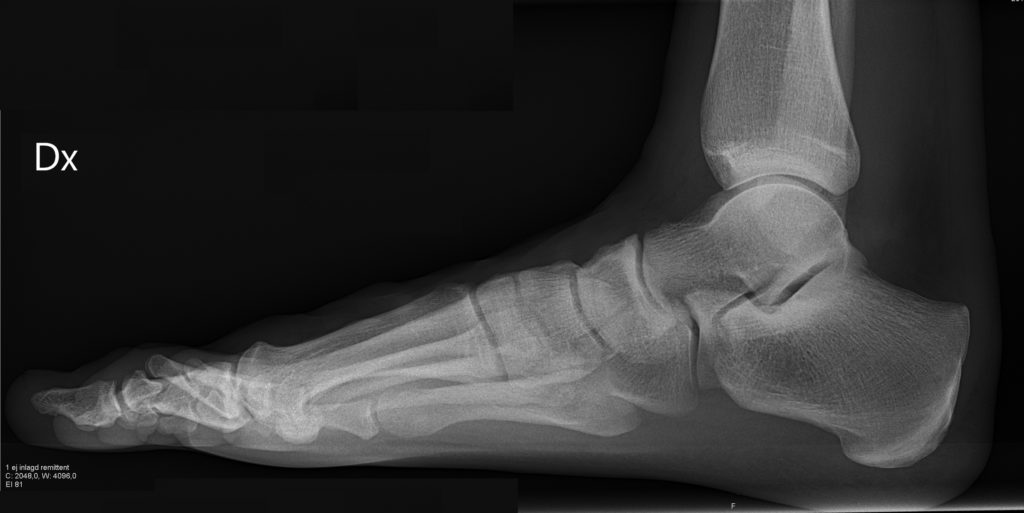

Когда человек жалуется на дискомфорт и неприятные ощущения во время ходьбы, врач должен в любом случае направить его на рентген стопы. При затруднении движения и чрезвычайно сильной боли данная процедура выполняется с нагрузкой. Чтобы диагностировать существующую проблему, снимки выполняются в различных проекциях.

Процедура рентгена стопы не требует большого количества времени. Пациента просят встать одной ногой на специальный диск, а вторую согнуть в колене. Нахождение в этом положении приводит к тому, что вес туловища перемещается на обследуемую конечность. Это позволяет максимально отразить всю картину состояния стопы. Пациент надевает защитный фартук, что делает обследование абсолютно безопасным. Обычно делаются такие виды снимков, как:

- Задне-передний, выполненный в двух проекциях.

- Боковой.

- Тыльно-подошвенный.

- Косой с разных ракурсов.